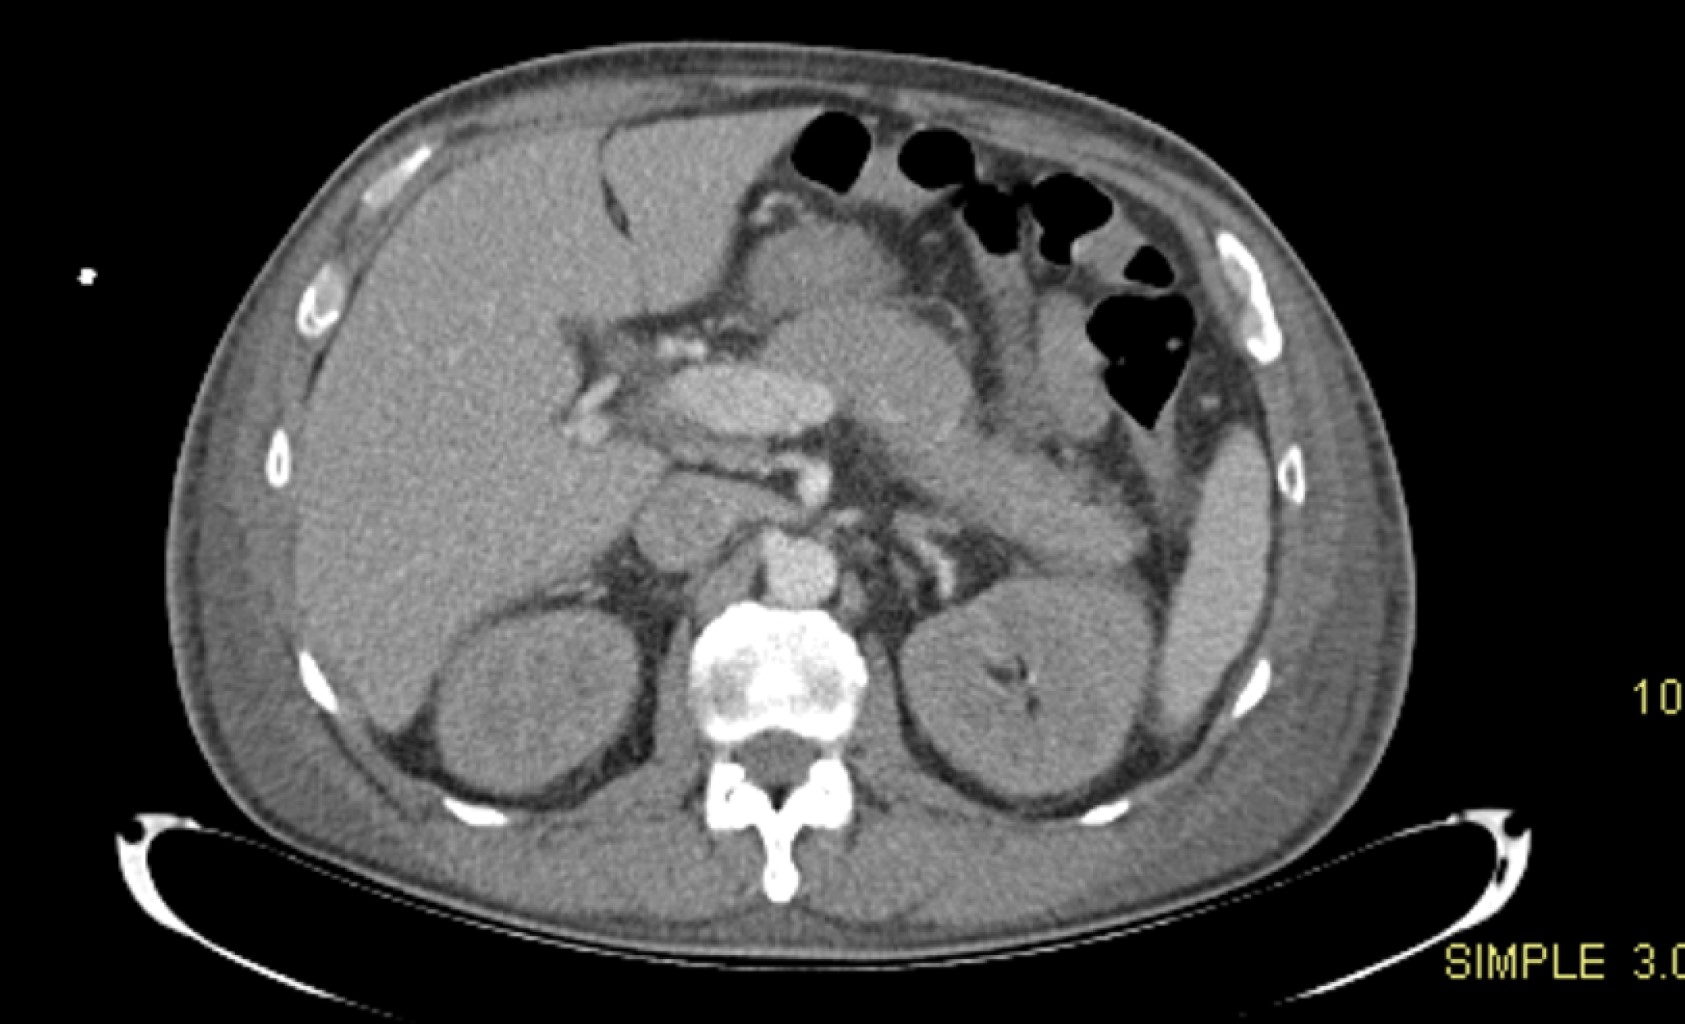

En la UTI se diagnosticó pancreatitis aguda, con base en criterios de Atlanta; elevación de enzimas pancreáticas, lipasa > 1,400 UI/L y estudio tomográfico de abdomen, donde se estadificó como pancreatitis aguda Balthazar C (Figura 1), con datos de severidad por presencia de datos de disfunción orgánica, disfunción renal y hepática.

Figura 1